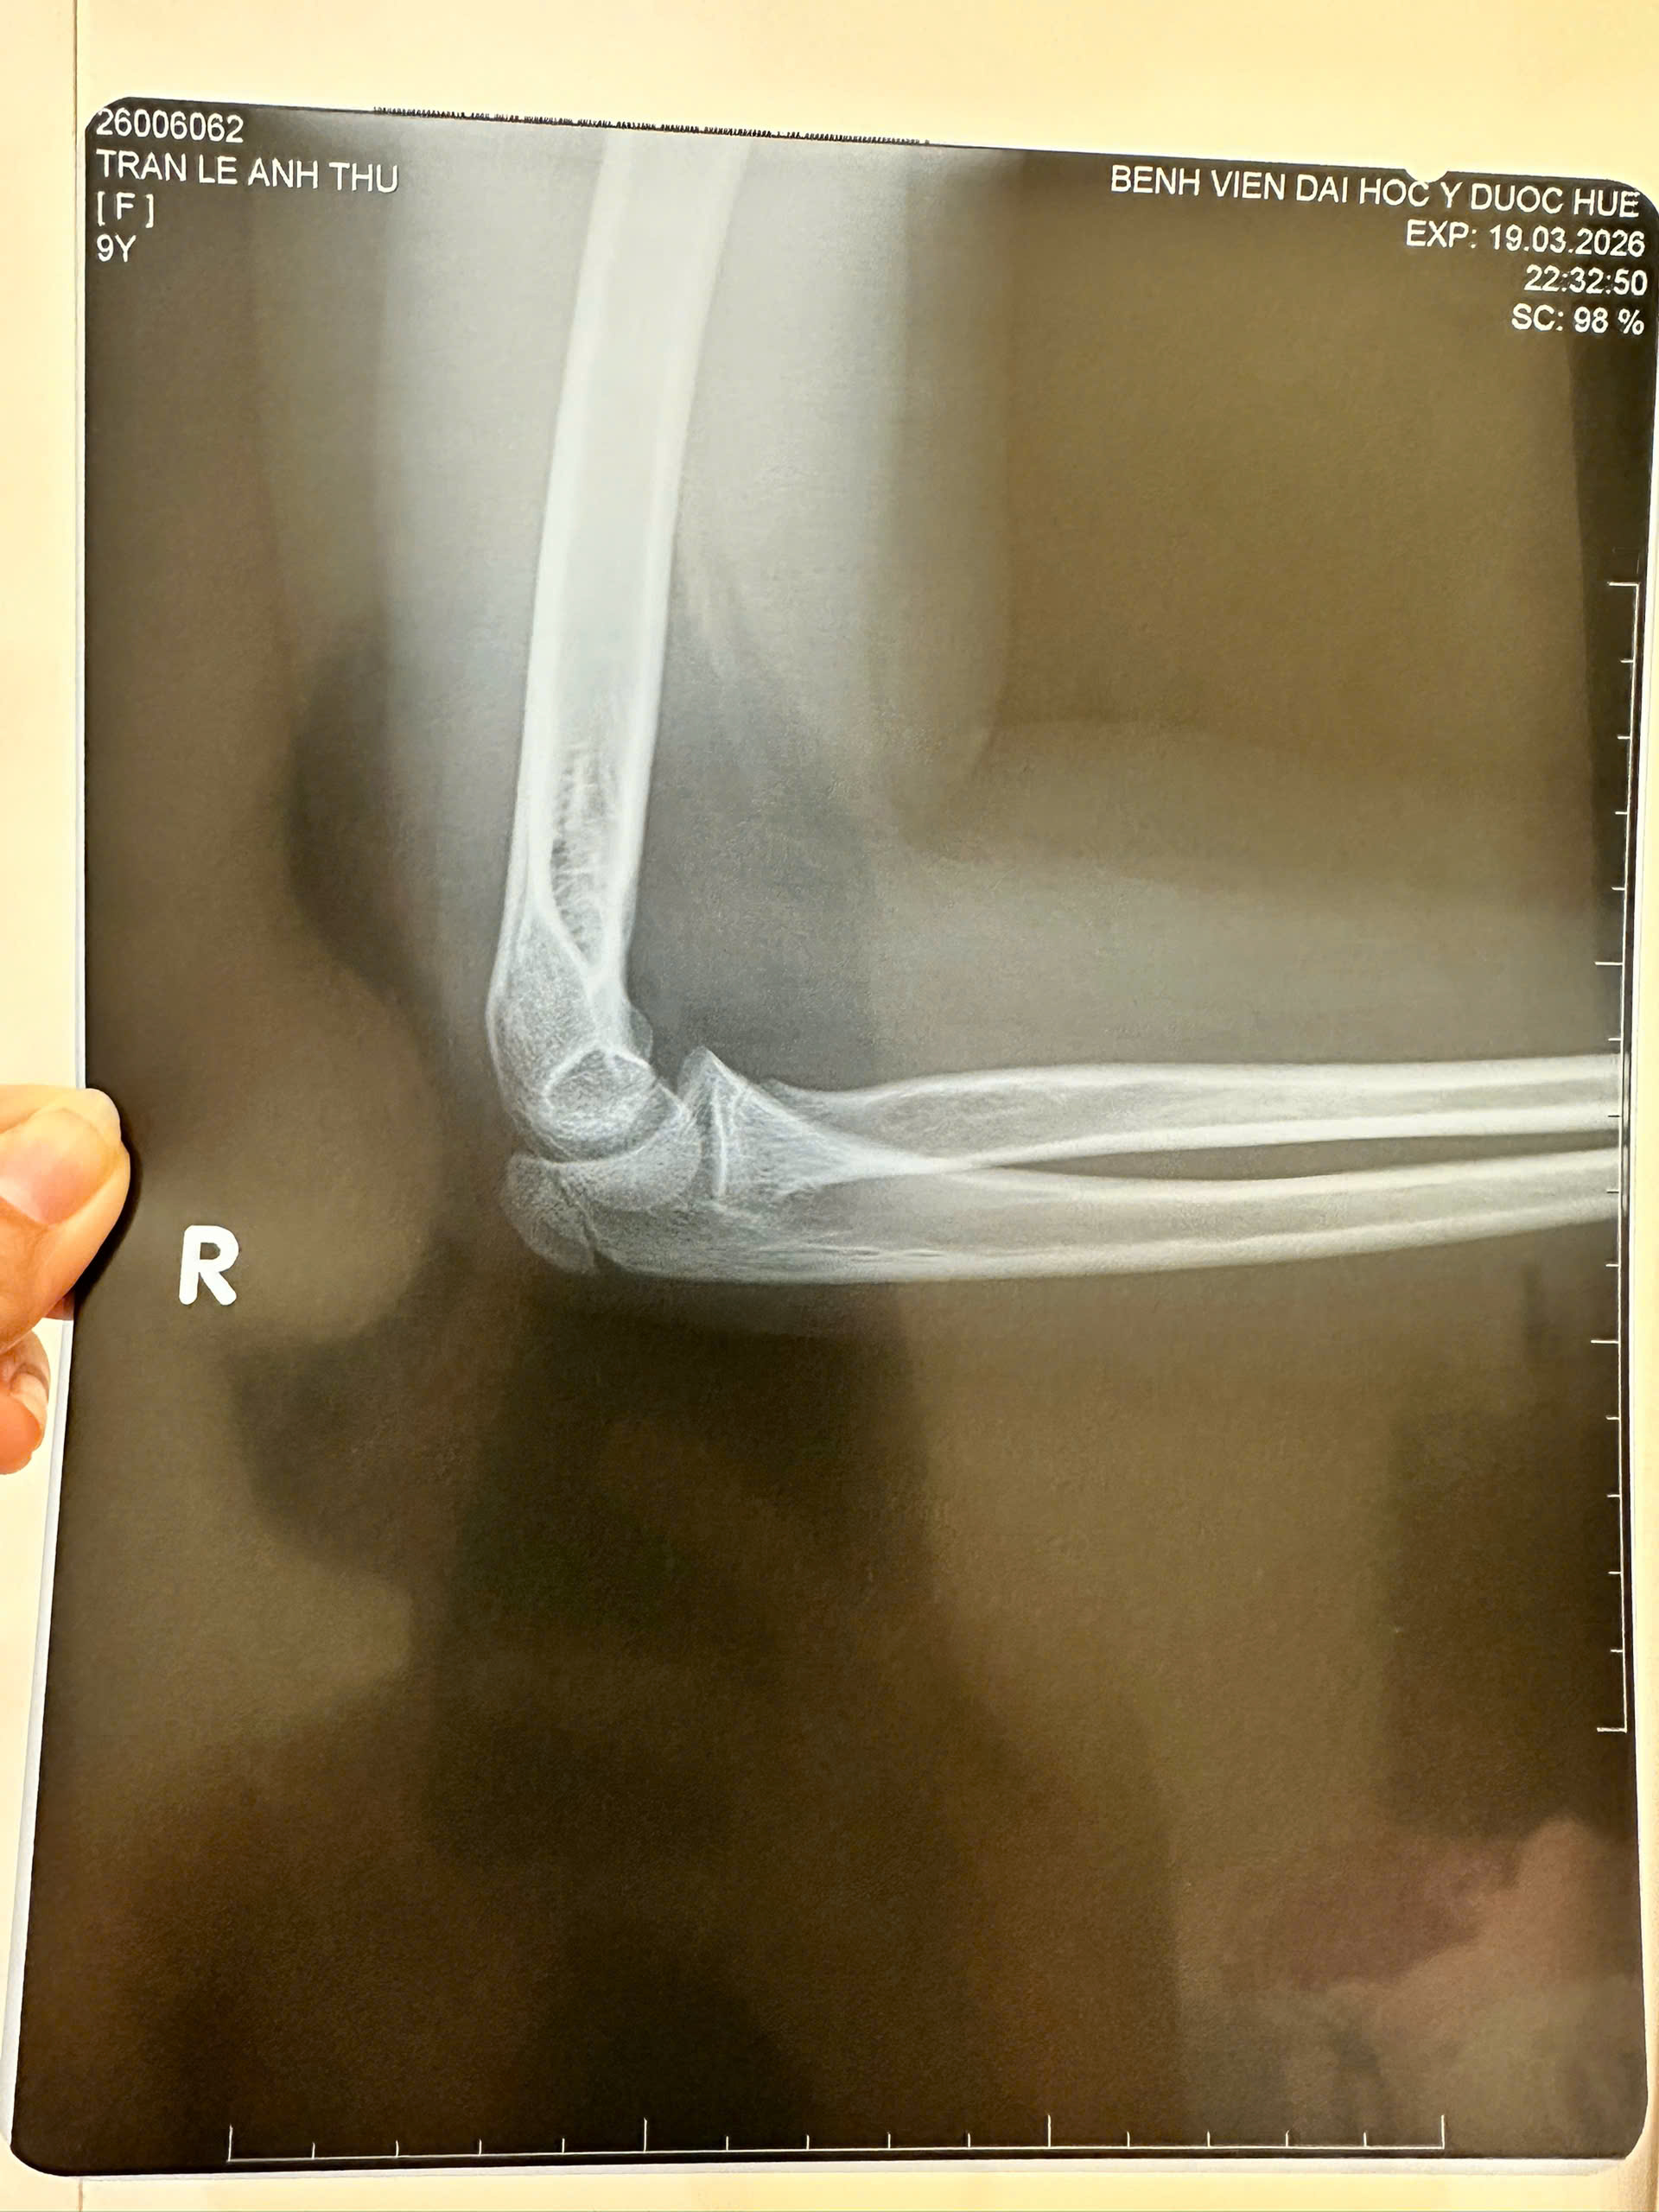

Chiều tối ngày 19/3/2026, mẹ của em Anh Th.. thông báo cho giáo viên chủ nhiệm về việc em Th.. bị đau ở tay, sau đó gia đình đưa cháu đi kiểm tra ở Bệnh viện Đại học Y - Dược Huế, và kết quả chụp X-quang ghi nhận “gãy mõm khuỷu xương trụ phải, ít lệch chuyển”, trong khi đó, đơn thuốc thể hiện bệnh nhân bị “chấn thương khuỷu tay phải và cổ tay phải”, cho thuốc Hapacol 150mg (uống khi đau) và mua đai treo tay 1 tuần.

Với tinh thần đó, sáng ngày 24/3/2026, Bệnh viện Đại học Y - Dược Huế có Giấy chứng nhận thương tích số 001/26/BVYD ngày 23/3/2026 đối với em Trần Lê Anh Th.., ghi kết quả như sau: “Tiền sử bệnh: Gãy xương ở khuỷu tay phải lúc 3 tuổi; Chẩn đoán: chấn thương khuỷu tay và cổ tay phải; Phương pháp điều trị: Xử trí: Treo tay 01 tuần, uống thuốc theo đơn; hẹn tái khám… tại phòng khámNgoại chấn thương; Tình trạng thương tích, tổn thương lúc vào viện: Trẻ tỉnh táo, huyết động ổn, sưng đau khuỷu và cổ tay phải; Tình trạng thương tích, tổn thương lúc ra viện: Trẻ tỉnh táo, huyết động ổn, đã treo tay”. Căn cứ vào kết luận của Bệnh viện Trường Đại học Y - Dược Huế, thì thông tin giáo viên dùng thước đánh gãy tay học sinh tại trường TH Vĩnh Ninh là không đúng sự thật.